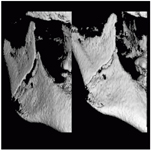

Je speciální zubní digitální tříprostorový tomograf (3D), který umožňuje na základě jediného snímkování vytvořit všechny typy RTG zobrazení, které jsou pro lékaře potřebné. Díky používané technologii tzv. „kuželového paprsku“ a speciálním senzorům je výrazně zmenšená dávka záření - o více jak 80% proti klasickému CT vyšetření. To je významné zejména u dětí. Pomocí tohoto přístroje je možné zjisti skutečnou situaci v čelistních kostech pacienta tedy množství kosti - můžeme změřit skutečnou šířku i výšku kosti, i kvalitu kosti (hustotu) v místě uvažované implantace. 3D (tříprostorové) zobrazení umožňuje zvýšit prostorovou představu operatéra ještě před vlastní operací a zároveň pacientovi lépe objasnit a ukázat oblast plánovaného zavedení implantátu.

Pacient „neumí číst“ RTG snímky, ale díky 3D zobrazení vidí „svoji skutečnou čelist“ - např. jak je nízká či úzká, vidí průběh nervu nebo velikost čelistní dutiny, což mu umožní i pochopení nutnosti v některých případech provést pomocné zákroky ještě před vlastním zavedením implantátu (viz. kostní štěp, sinus lift, kostní granulát...).

Vyšetření pomocí tohoto přístroje používáme i ve stomatochirurgii (zlomeniny čelistí, zuby moudrosti, cysty, onemocnění čelistního kloubu), ortodoncii (retinované zuby, nadpočetné zuby), parodontologii atd.